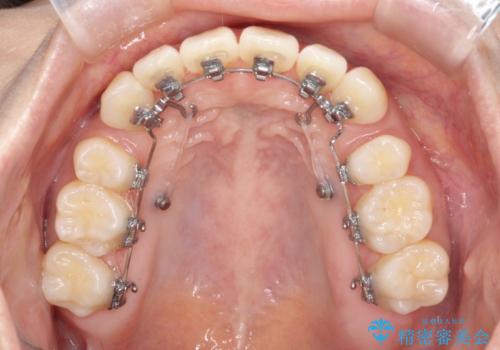

- 出っ歯、ガタツキ、噛み合わせが気になるとのことで来院された患者様です。

小臼歯を抜歯することでスペースを作り、前歯を下げて口元を下げ、Eラインを改善する治療方針としました。

表側のワイヤーは見た目が気になるとのことで、上の歯だけ裏側に付くハーフリンガルという装置で治療を行いました。